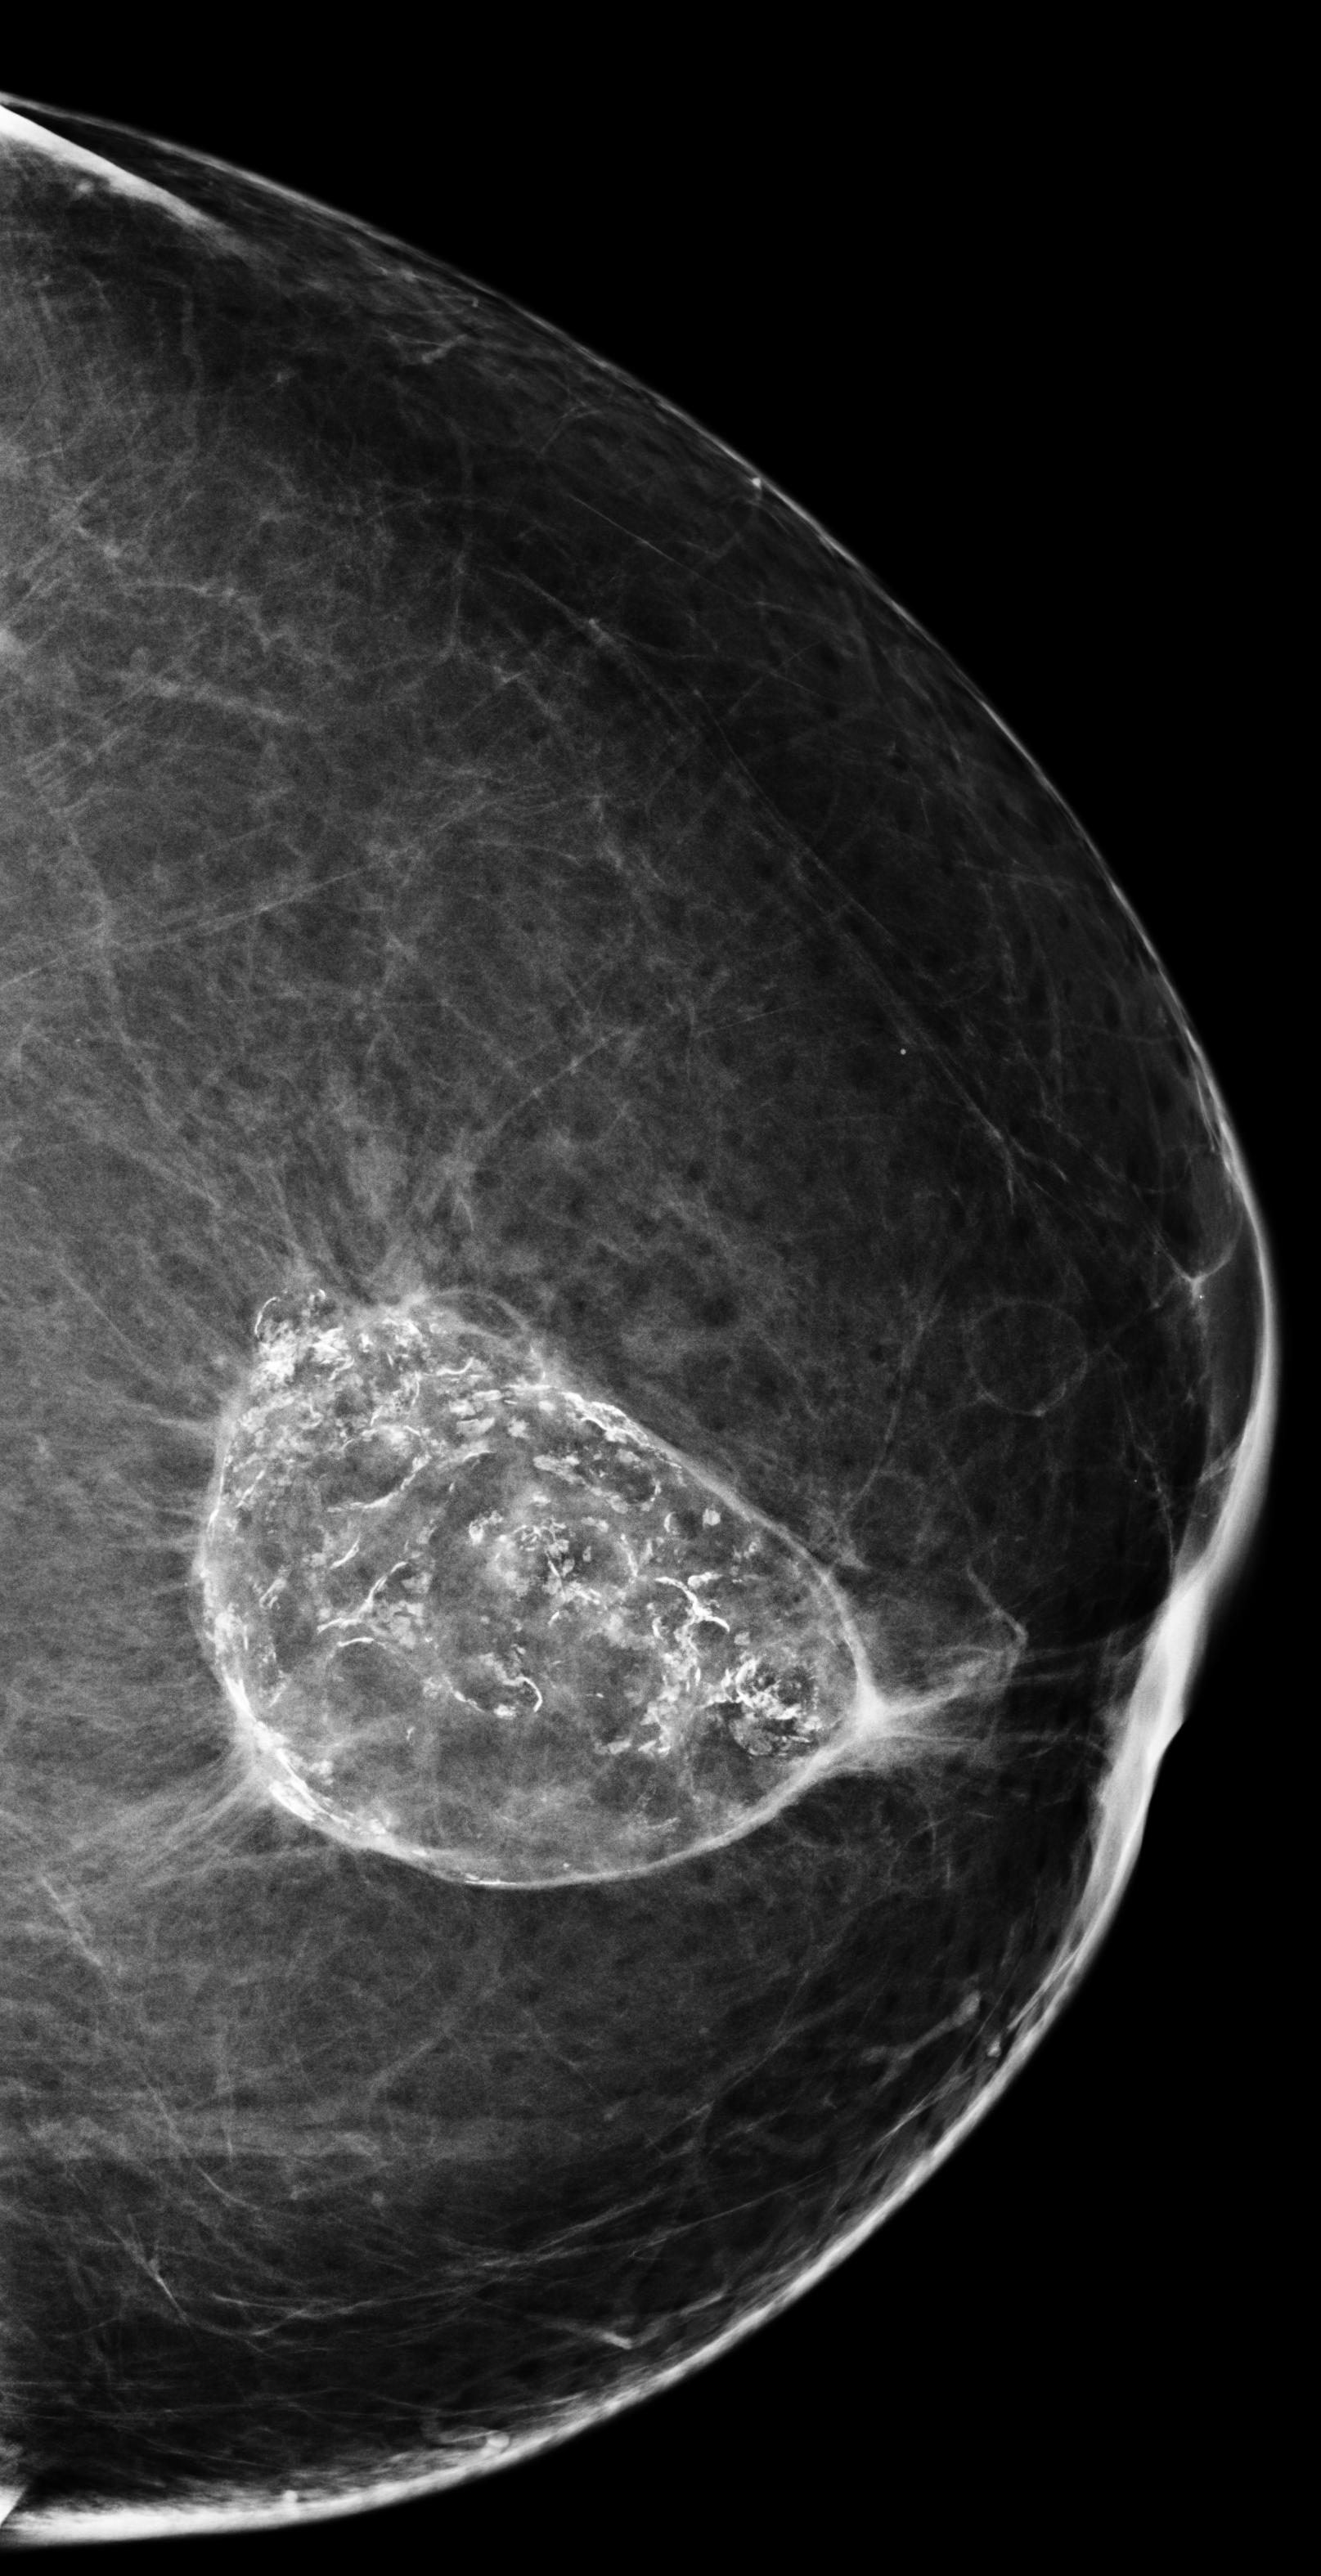

The results from all three models are shown in \tablereftab:example. AlignLocalCompare performs better for malignant prediction than the single-exam baseline and GlobalCompare, in both the biopsied and screening populations. We do not observe improvement for benign category–we speculate that this is because our model learns to focus on regions with significant changes, but not many changes accompany benign findings. In \figurereffig:exams, we visualize a few cases where the AlignLocalCompare is more confident in its prediction than the single-exam baseline Wu et al. (2019a). For \figurereffig:exams(a), we observe that the malignant region did not exist in the prior exam. For \figurereffig:exams(b), we observe that the bright spot at the center already existed in the prior exam, and the model can be more sure that it is not malignant.

[\capbeside\thisfloatsetupcapbesideposition=left,top,capbesidewidth=6cm]figure[13cm] prior latest highlight prior latest L-CC Refer to caption Refer to caption Refer to caption L-CC Refer to caption Refer to caption L-MLO Refer to caption Refer to caption Refer to caption L-MLO Refer to caption Refer to caption (a) (b)

Figure 3: Test examples where AlignLocalCompare performs better than the single-exam baseline. A breast with a malignant finding shown in (a) (malignant finding is highlighted with red) and one with a benign lesion shown in (b). AlignLocalCompare predicts malignancy with 0.97 probability for (a) and 0.04 for (b), whereas the baseline predicts 0.73 for (a) and 0.24 for (b). There is about a year gap between two exams for both patients.